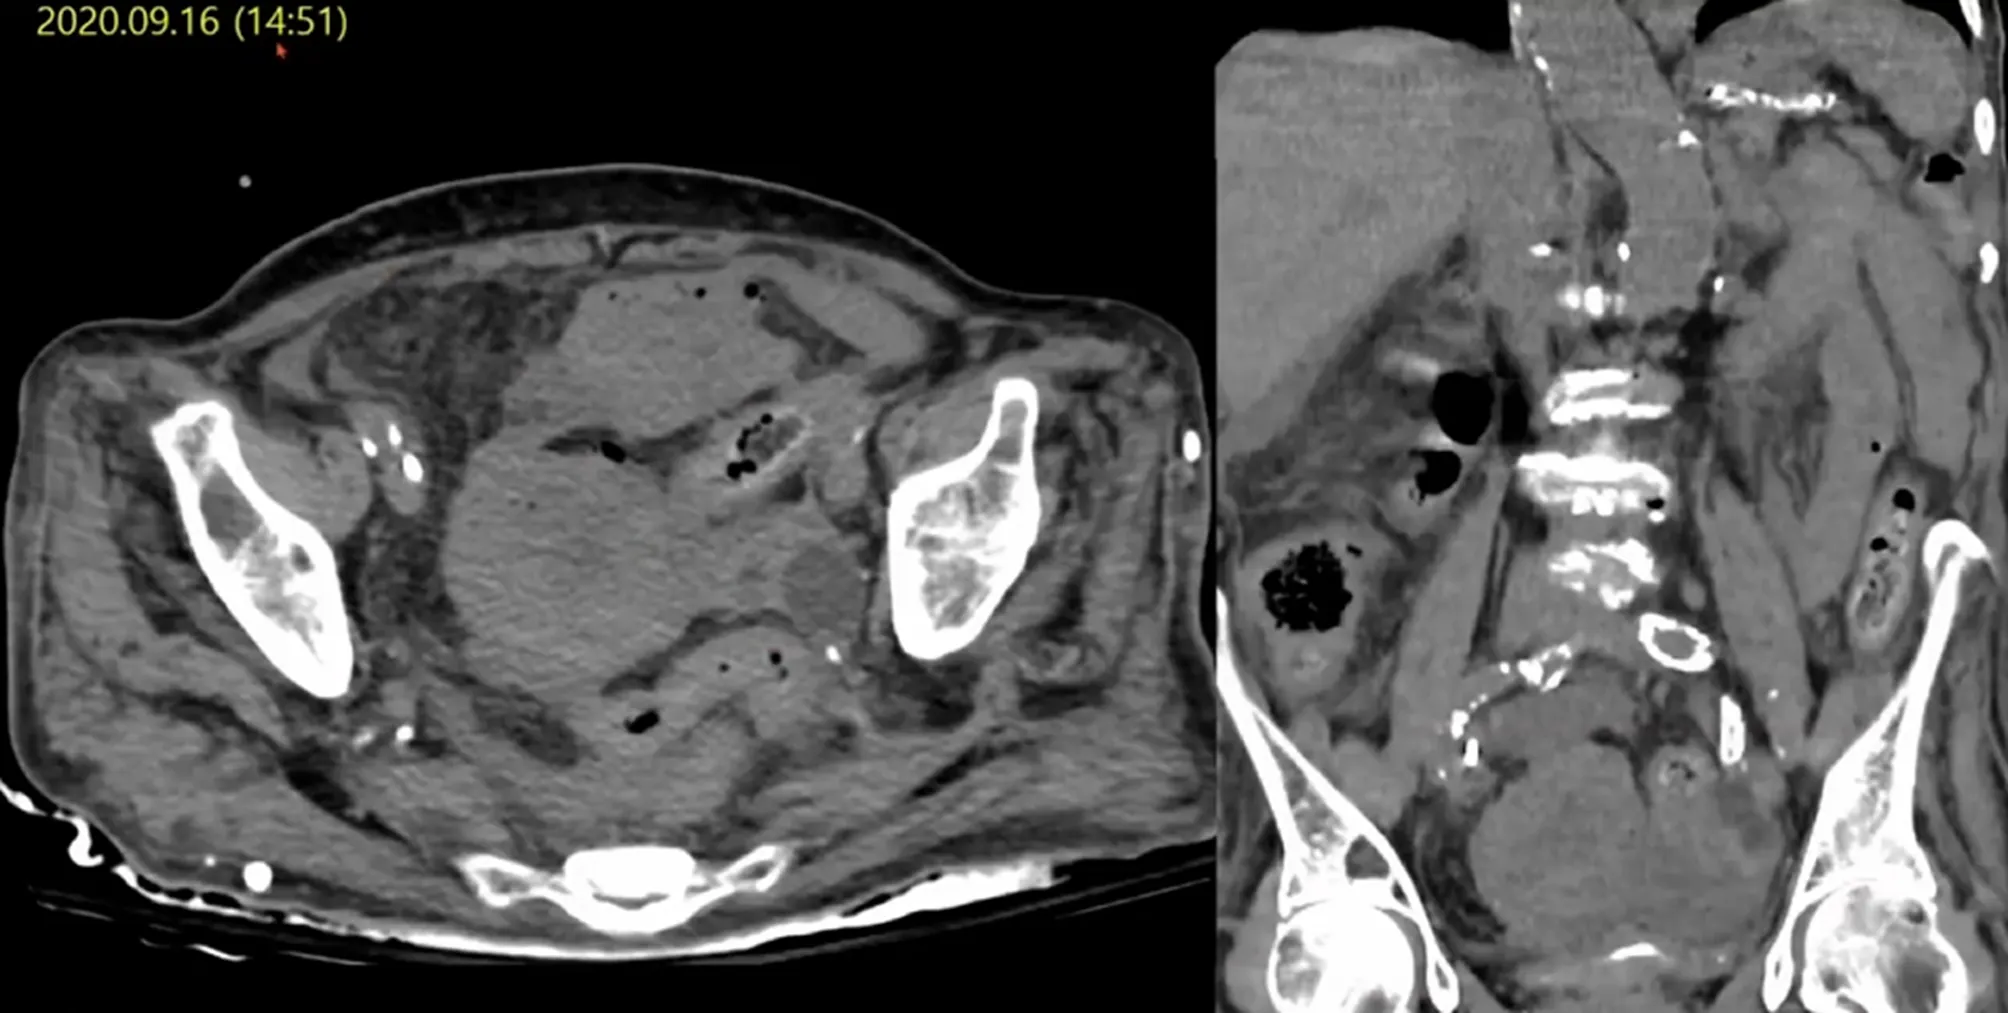

Case 9

•

F/87 C/C: hematemesis

Hx: HTN, DM, Asthma, h/o MI, A.fib

Lab : WBC 30k , Hb 7.9 , CRP 6.9 , INR 1.7

EGD

Acute hemorrhagic gastritis, no current bleeding

R/O gastric angiodysplasia, body

Aggravation of abdominal pain ⇒ F/U with non-contrast CT

Uterus rupture

Uterine rupture by inflammation

Etiology

◦

Trauma

Genetic disorder associated with uterine wall weakness

Prolonged induction or augmentation of labor

Overstretching of the uterine wall (multiple gestation pregnancy, uterine anomalies ..)

Spontaneous rupture of pyometra causing peritonitis in elderly female

Misdiagnoses are common , most frequent preoperative diagnosis is generalized peritonitis secondary to GI perforation